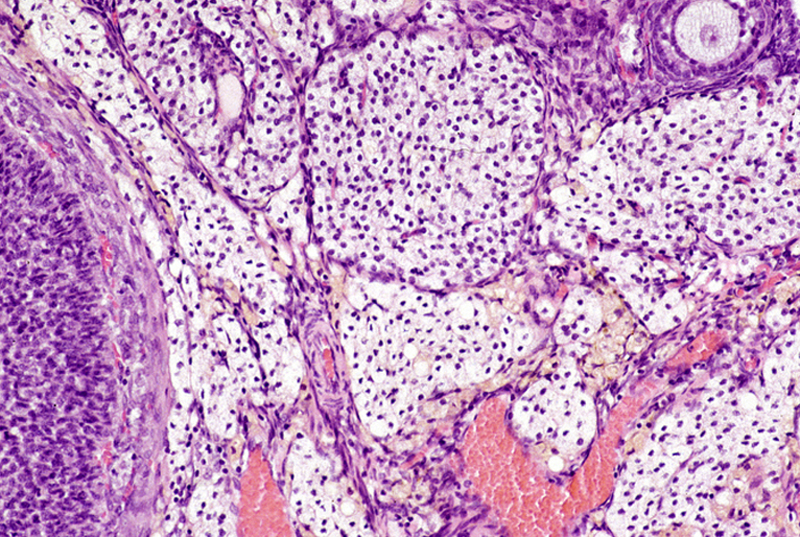

Etichettato per decenni come semplice “tessuto connettivo”, l'interstizio era rimasto “invisibile” nella sua complessità a causa dei metodi usati per esaminarlo al microscopio, che lo facevano apparire erroneamente denso e compatto.

La sua vera natura è stata invece osservata per la prima volta grazie ad una nuova tecnica di endomicroscopia confocale laser, che consente di vedere al microscopio i tessuti vivi direttamente dentro il corpo, senza doverli prelevare e poi fissare su un vetrino. Impiegata su alcuni pazienti malati di tumore che dovevano essere sottoposti a chirurgia per rimuovere pancreas e dotto biliare, la tecnica ha permesso di osservare la reale struttura dell'interstizio, che è stato poi riconosciuto anche in tutte le altre parti del corpo sottoposte a continui movimenti e pressioni. Alla luce della sua complessità, l'interstizio si è così meritato la “promozione” ad organo.